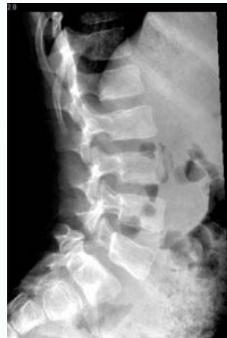

- Lateral view: Shows vertebral slip

- Spondylolisthesis: Anterior vertebral displacement